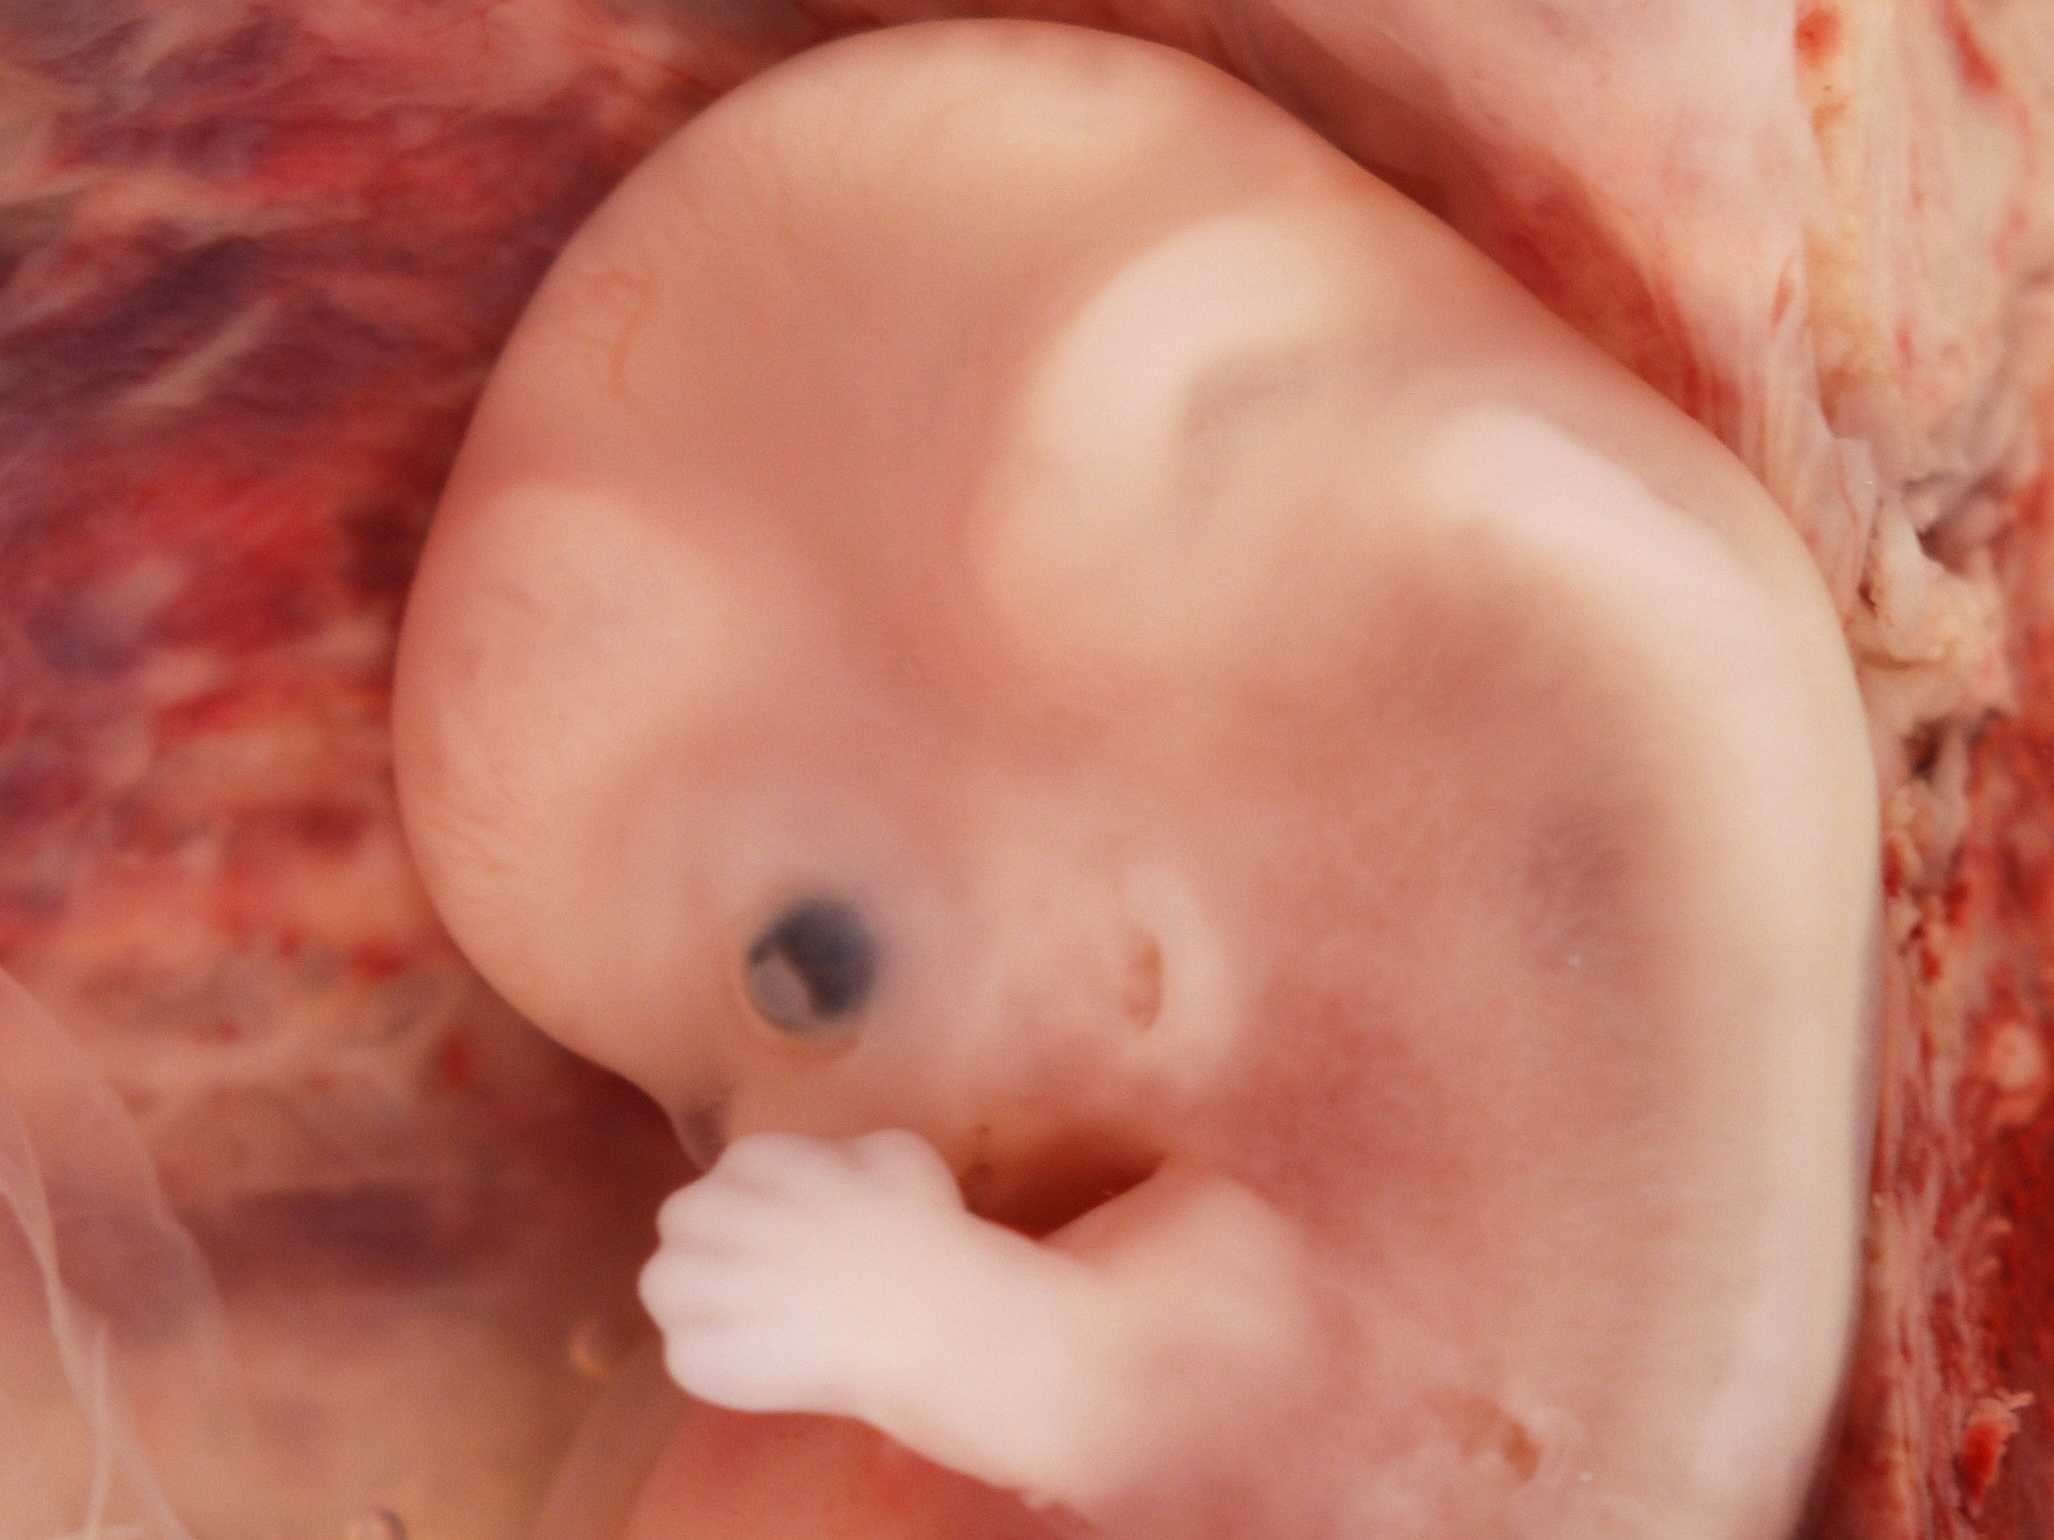

Эмбрион на 8 неделе беременности

Человеческий эмбрион на 8 неделе беременности

Эмбрион на 8 неделе беременности

Эмбрион на 8 неделе беременности